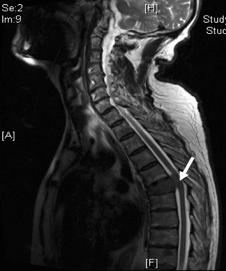

随后血常规、尿常规、肝肾功能电解质都显示出没什么问题。胸椎平片显示T6和T7椎体塌陷,伴有椎旁软组织病变。脊柱MRI显示T6椎体塌陷,原来的位置被肿块占据,并向后延伸至椎管内,压迫了鞘囊和脊髓的前部(图1)。另外L4椎体也有些许局限性受累。

图1 脊柱MR T2加权矢状面。T6塌陷。T6椎体被肿块所取代,向后延伸到椎管,压迫了鞘囊和脊髓的前部。可清楚地看到肿块病变延伸至脑脊液(正常脑脊液T2加权图像为白色),并压到了脊髓。